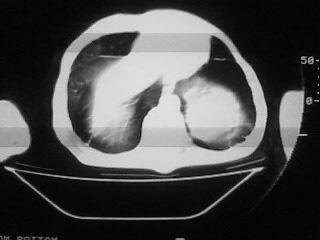

m,45,咳嗽、气憋月余。先天性畸形

1)两肺上叶继发性肺结核,部分肺间质纤维化。2)慢性支气管炎。3)肺气肿,两上肺多发性肺大泡。4)右侧胸膜增厚可能。5)脊柱上胸段畸形。

考虑:1)两肺上叶继发性肺结核,部分肺间质纤维化。2)慢支肺气肿并两上肺多发性肺大泡。3)右侧胸膜增厚可能。5)脊柱上胸段畸形。

补充一下,病人有强直性脊柱炎十多年

慢支炎、肺气肿、间质纤维化,双肺结核,脊柱侧弯

脊柱侧弯后突畸形,1)两肺上叶继发性肺结核,部分肺间质纤维化。2)慢支肺气肿并两上肺多发性肺大泡。3)右侧胸膜增厚可能。5